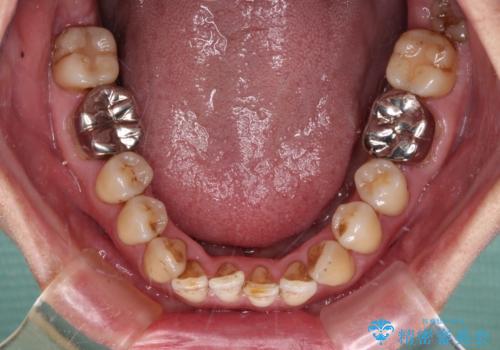

- かつて抜歯矯正を行ったものの、後戻りをしてしまったとのことで来院された患者様です。

上顎前歯が前突し、隣の歯が裏側に移動してきている状態でした。

飲み込みの状態を確認したところ、舌の突出癖が認められたため、それによる後戻りの可能性が高いと考え、舌のトレーニングを指導しました。

日頃から飲まれる飲み物の影響で着色しやすいため、来院の度に着色除去のクリーニングも行っていました。